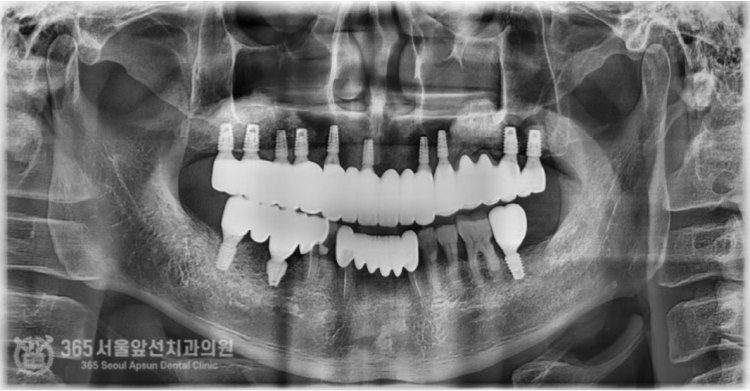

촬영일시: 2024.10.14. 충분한 기간이 지나서 잇몸을 열어보았습니다. 제대로 생성된 상악동 부위의 뼈를 볼 수 있습니다. 이 사진을 보여드리니 환자분께서 매우 놀라하시며 기뻐하셨던 순간이 생생합니다 ㅎㅎ 촬영일시 : 2025.02.10. 치료가 종결되고 난 후의 엑스레이 사진입니다. 기존에 타병원에서 실패했던 상악동 골이식 자리에 대한 처치와 임플란트 식립까지 완벽하게 이루어진 것을 볼 수 있습니다. 오늘도 기억에 남는 환자분의 증례를 소개해드렸습니다. 앞으로 좋은 증례로 찾아뵙겠습니다. 지금까지 365일 열린 가까운 서울대학교 치과병원을 지향하는 간석동치과 365서울앞선치과였습니다. 감사합니다. [ 치료기간 : 2024년 6월 14일 ~ 2025년 2월 10일 ] ※ 365서울앞선치과의원의 모든 포스팅은 각 진료과 의료진이 직접 작성합니다. 365서울앞선치과의원 블로그의 임상 케이스 게시물은 환자분께 의학적으로 정확하고 상세한 정보를 드리기 위해 각 진료과 의료진이 직접 작성하며, 모든 증례 사진은 본원 의료진이 직접 시술한 증례를 촬영한 것으로, 의료법 제23조, 제56조에 의거하며 환자분의 동의를 얻어 포스팅에 사용하였습니다. 또한 해당 케이스는 본 환자분의 치료 결과이며, 환자 상태에 따라 치료의 결과는 달라질 수 있습니다. |